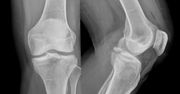

Mechanizm złamania kości